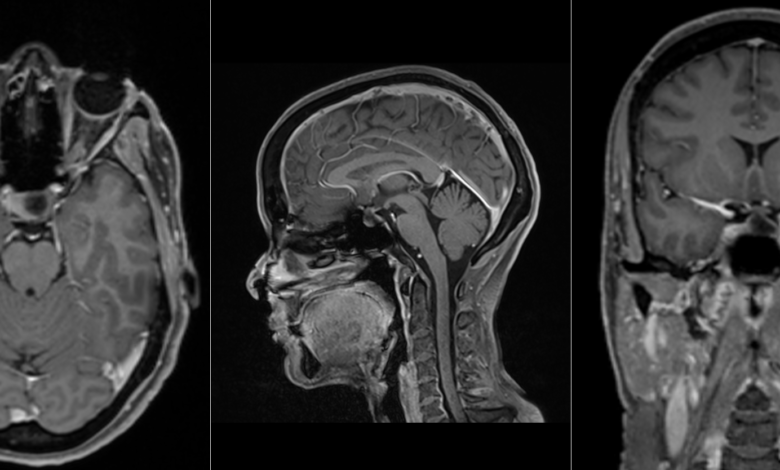

ام آر آی هیپوفیز یکی از اقدامات اقدامات ام آر آی سر و گردن به شمار می آید. ام آر آی غده هیپوفیز راهکار اصلی تشخیص تومور هیپوفیز است. غده هیپوفیز بافتی در قسمت زیرین مغز و اندازه ای در حدود یک نخود است. هیپوفیز (Hypophysis) با کارکردهای مهمی نظیر رشد در دوران کودکی و یا تولید مثل در ارتباط است.

ام آر آی هیپوفیز یک روش تصویربرداری پزشکی است که در آن از غده هیپوفیز و ناحیه های در مغز تصویربرداری می شود. همانطور که گفته شد، غده هیپوفیز در قسمت زیرین مغز و دارای اندازه ای در حدود یک نخود است.

شکی وجود ندارد که هیپوفیز یکی از مهمترین بخش های مغز محسوب می شود و بیماری های آن می تواند مشکلات زیادی را برای سلامتی ایجاد نماید. با استفاده از MRI غده هیپوفیز، پزشک می تواند تومور هیپوفیز را در صورت وجود، تشخیص دهد. به طور کلی برای تعیین اندازه و نوع اغلب تومورهای ماکروآدنوم و میکروآدنوم از ام آر آی Hypophysis استفاده می شود.

MRI غده هیپوفیز یک روش کارامد برای تشخیص بیماری های مربوط به غده هیپوفیز و تومورهای ماکروآدنوم و میکروآدنوم است. ام آر آی غده هیپوفیز به عنوان زیرمجموعه از MRI سر و گردن با به روزترین متد تصویربرداری تحت نظارت اساتید دانشگاه علوم پزشکی تهران در رشته های مرتبط، در مرکز تصویربرداری پزشکی تهران۱۰۱ انجام می شود.